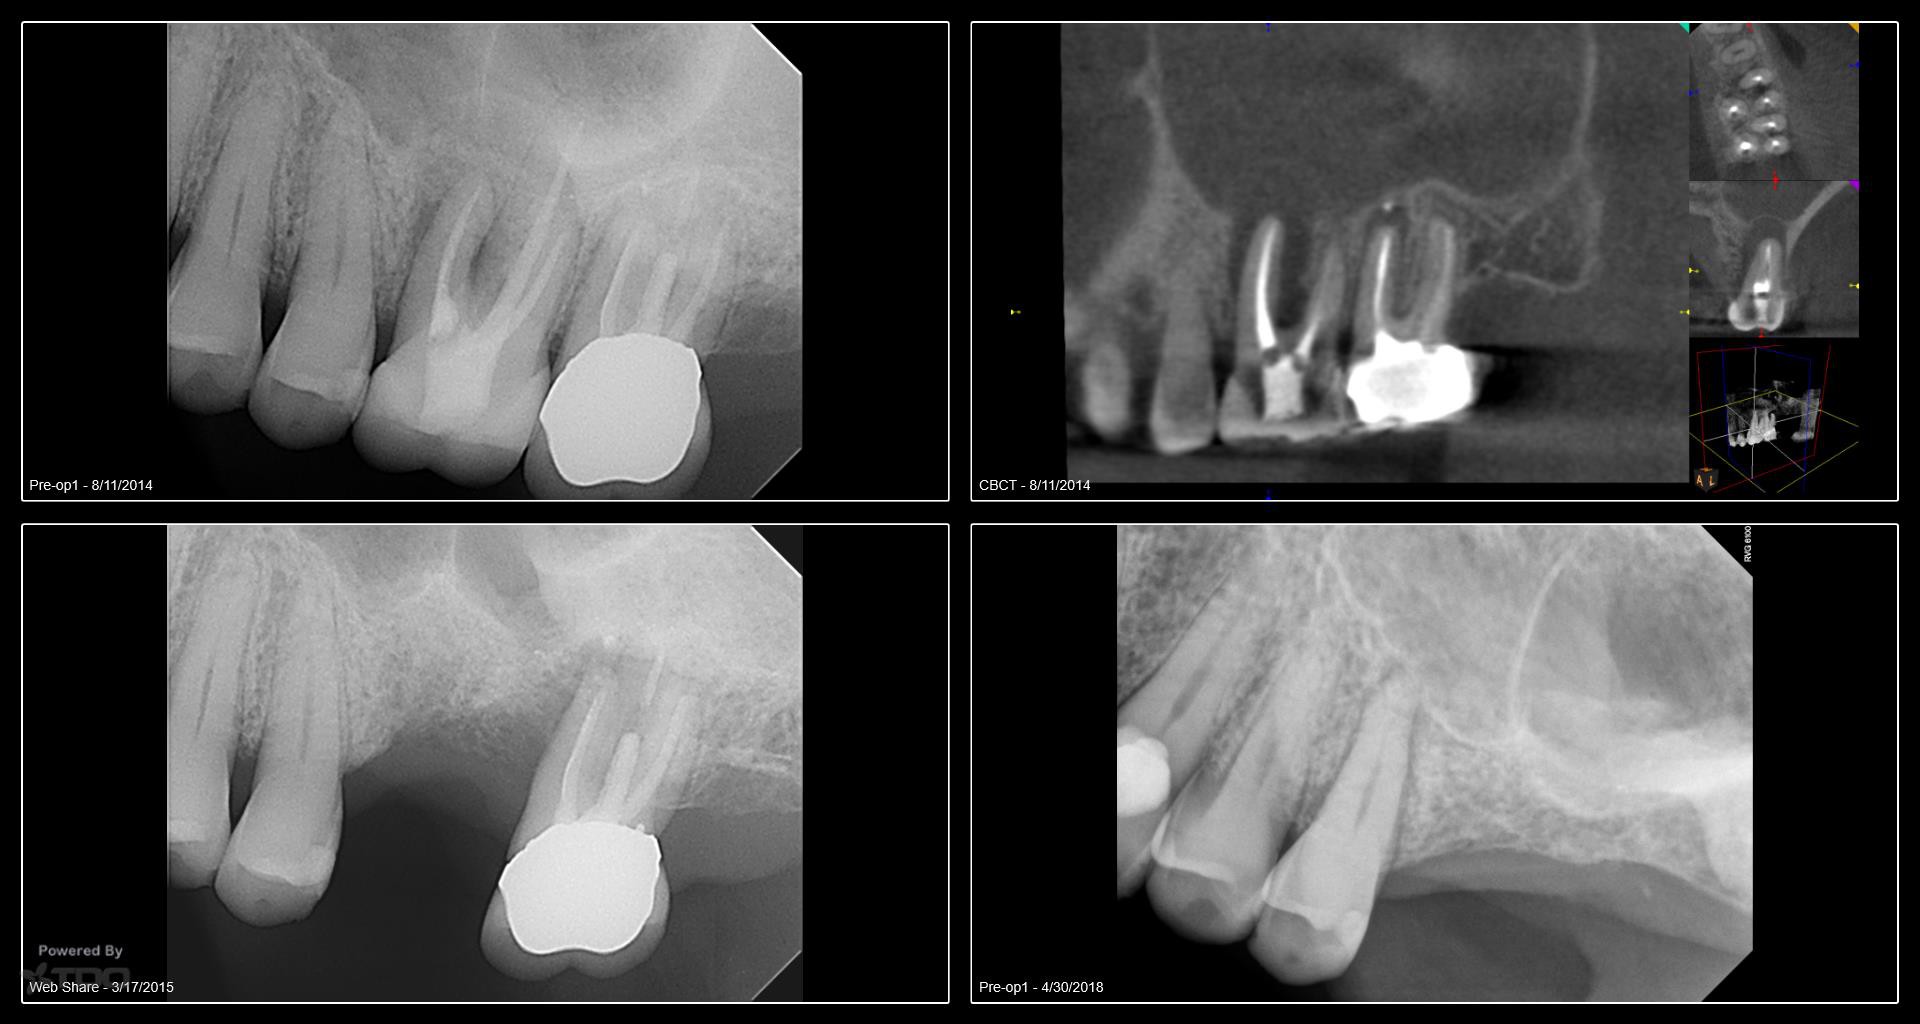

I began seeing this patient in 2014. Tooth #14 was diagnosed with a vertical root fracture at that time and the tooth was removed and the site grafted. He then presented in 2015 with a VRF of #15. It was removed and we discussed an implant in the #14 site. He did not follow up with the implant. He presented earlier this year with a vertical root fracture of #13. The tooth was removed in April and implants were placed today. Internal sinus lifts were performed for both #’s 13 and 14. I will uncover in 4 months. We have also discussed the importance of a night guard. Hopefully he will follow through with the guard. -Charles

Do you have the trephines for me on this case?